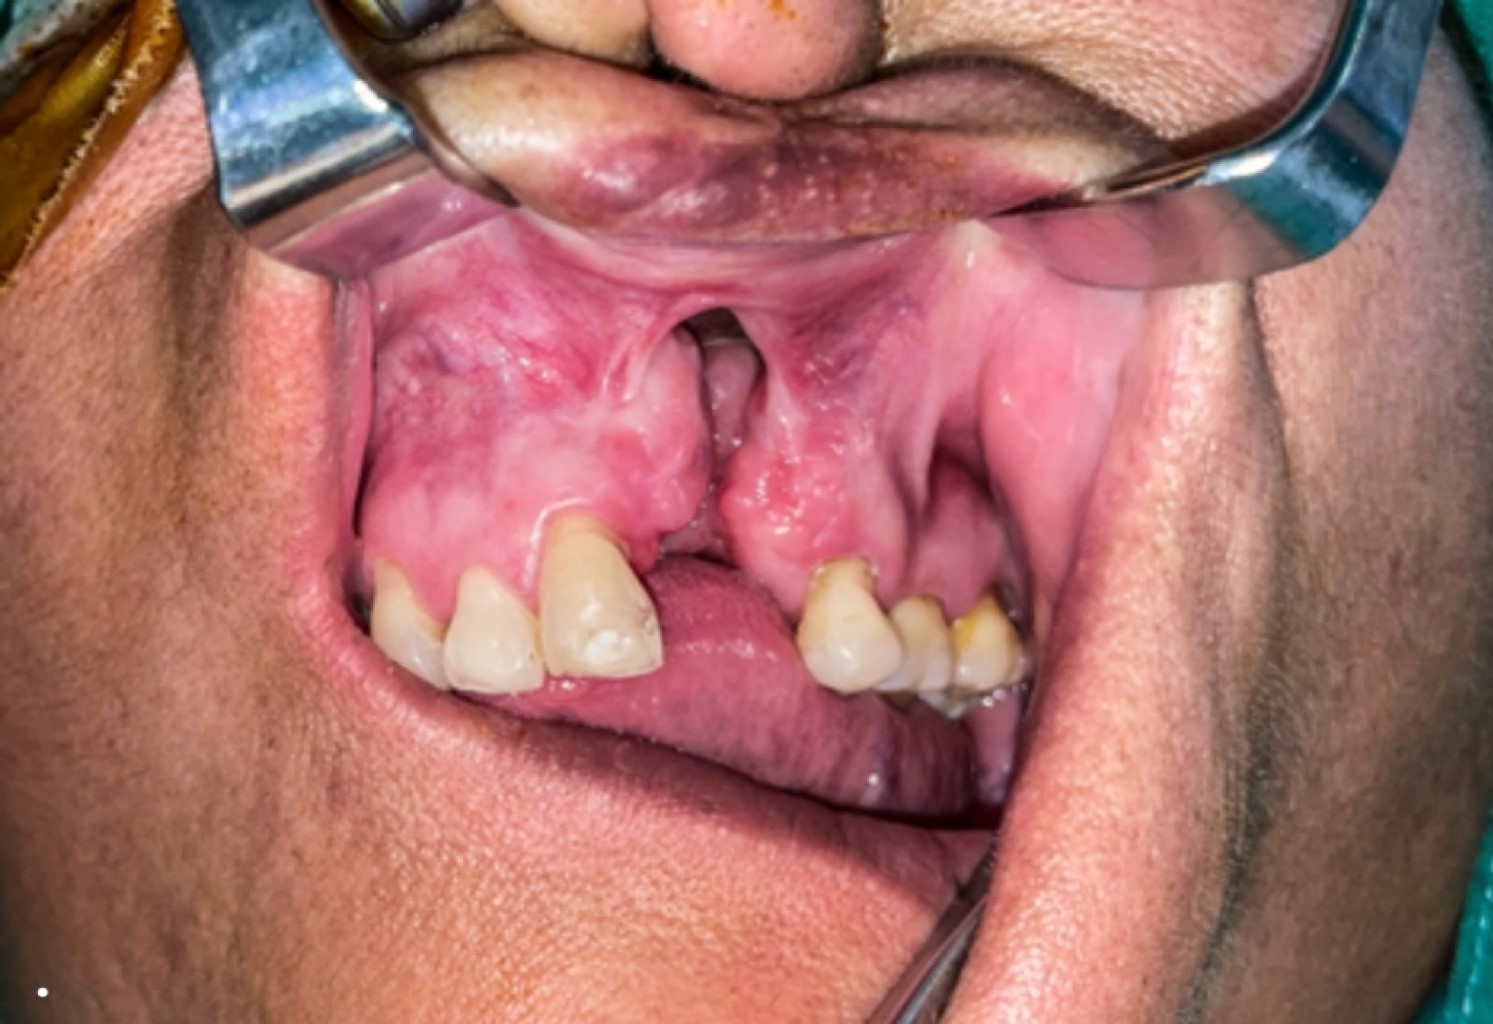

Paciente 1: sexo femenino, 56 años, con antecedentes de artritis reumatoide y FLP unilateral, sometida a queiloplastia primaria y palatoplastia en un tiempo quirúrgico. Al examen clínico evidencia fisura de reborde alveolar de 10 mm de diámetro transversal Pittsburg VI y VII (Figura 1), paso de líquido y alimentos sólidos desde la cavidad oral a la fosa nasal, trastorno que se remonta al nacimiento.

Paciente 2: sexo femenino, 52 años, con antecedentes de FLP unilateral, sometida a queiloplastia primaria y palatoplastia en un tiempo quirúrgico. Al examen clínico evidencia defecto de 13mm en su diámetro transversal Pittsburg VI y VII (Figura 2), con paso de líquidos y alimentos desde la cavidad oral a fosa nasal, además de alteraciones fonéticas importantes.